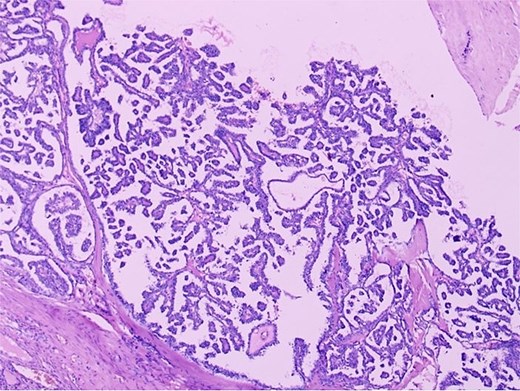

Histopathological section (H&E, ×40) demonstrating thyroid follicles of varying sizes filled with colloid material, consistent with struma ovarii comprising more than 50% of the ovarian tumour volume.

Histopathological examination confirmed a diagnosis of struma ovarii measuring 11 cm, within which a 1 cm focus of PTC was identified (Figs 2 and 3), exhibiting the characteristic nuclear features of PTC. No capsular or lymphovascular invasion was demonstrated, and the tumour was classified as Stage IA. Postoperative thyroid evaluation, including ultrasonography and thyroid function tests, was entirely normal.